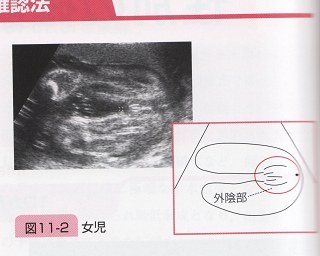

東京 テアトル 評判~杖 イラスト 無料;. 残念ながら我が家に女の子はいないので、とてもわかりやすい画像をゼクシィbabyよりお借りしました。 女の子の場合、 会陰部に”木の葉マーク”や”コーヒー豆”のような真ん中に何かしらの線が入っていることで判断 されます。. 解決済み 質問日時: 2014年2月2日 18:43 回答数: 1 閲覧数: 671.

女の子 の場合は、突起物はなく、 太ももの間に 木の葉のようなもの が見えます。 また、子宮と膀胱がふたつの黒い点として エコー写真に写ります。 ※女の子に恵まれれば、いつか写真参考アップしますね٩(•౪• ٩).